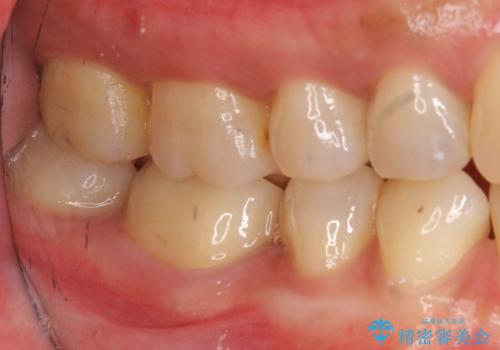

写真・レントゲン画像からもわかる通り、適合の良いクラウンを入れることができました。